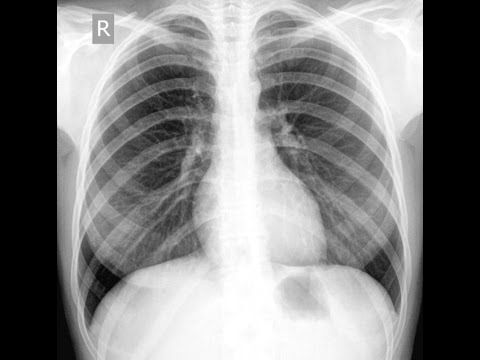

РОЗПІЗНАЙТЕ ОРГАНИ У ФРОНТАЛЬНІЙ ПЛОЩИНІ.

варіанти відповідей